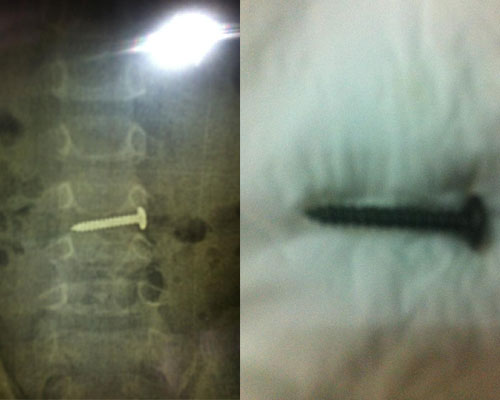

Chị Minh Ngọc ở Hà Nội vẫn chưa hết bàng hoàng kể lại, trong lúc chơi, bé Đào Gia Nghị 2,5 tuổi nhặt được chiếc ốc vít cho vào miệng. Khi phát hiện ra mẹ cháu đã nhanh chóng cho vào bệnh viện Bạch Mai cấp cứu. Kết quả chụp phim X-quang cho thấy chiếc ốc vít xoắn dài khoảng 2.5 cm đang nằm trong bụng cháu bé. Rất may đã lấy được chiếc ốc vít ra ngoài theo đường tiêu hóa.